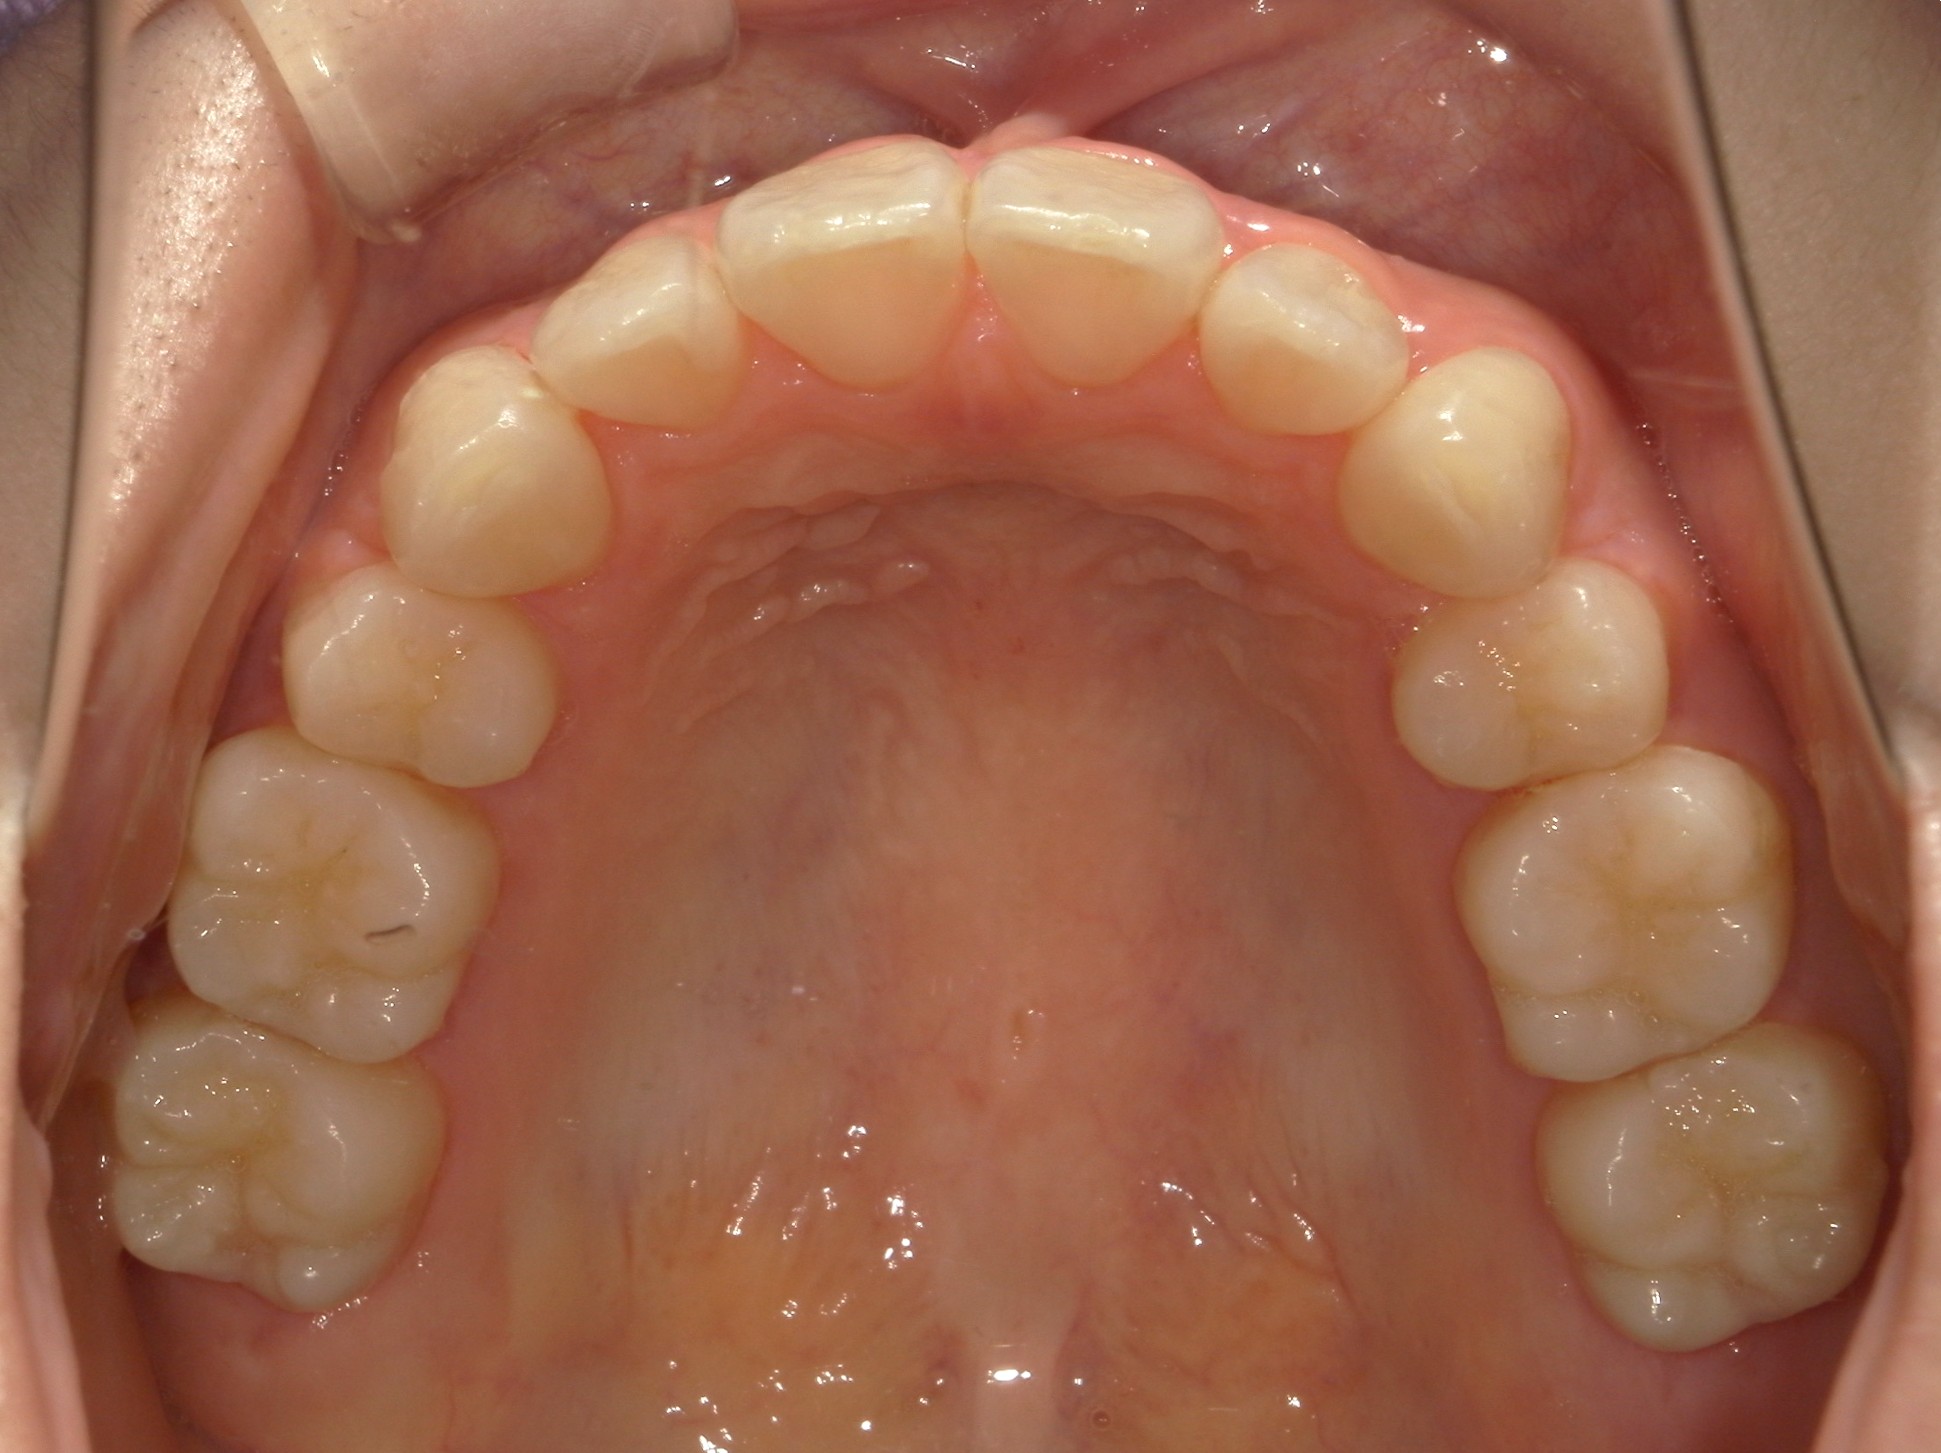

横から見た口腔内写真でよくわかるように、前歯が出っ歯になっており、全く咬んでいない状態でした。また下の前歯が本来4本あるところが、先天的に一本少なく3本しかない(Three incisors)であったため下顎のアーチが小さいというお口の状態でした。前歯を正しい傾きに治し、咬合させるため、上の歯のみ2本の抜歯を行うこととしました。下の前歯が3本のため、その正中に注意しながら前歯の傾きを修正し、奥歯のポジションを整えて仕上げました。口元の突出感は大きく改善し、咬合も良好な状態で完了することができました。

口内上

治療前

治療後